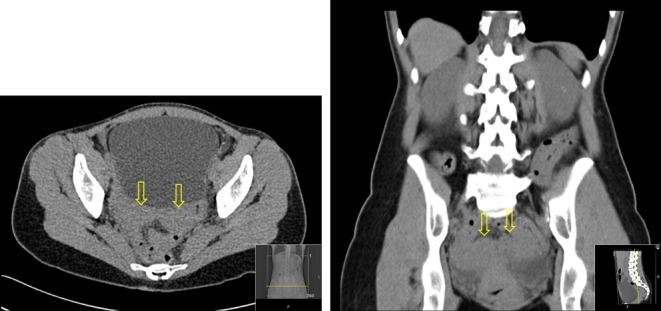

29-year-old female presenting with an 8-year history of unexplained hypomagnesaemia, which was severe enough to warrant intermittent inpatient admission for intravenous magnesium. Urinary magnesium was inappropriately normal in the context of hypomagnesaemia indicating magnesium wasting. Ultrasound imaging demonstrated unilateral renal cysts and computed tomography of kidneys, ureters and bladder showed a bicornuate uterus. Referral to genetic services and subsequent testing revealed a deletion.

一名29岁女性,有8年不明原因低镁血症病史,严重到需要间歇性住院静脉输注镁。在低镁血症情况下,尿镁异常正常,提示镁流失。超声成像显示单侧肾囊肿,肾脏、输尿管和膀胱的计算机断层扫描显示双角子宫。转诊至遗传服务部门并随后进行检测发现一个缺失。